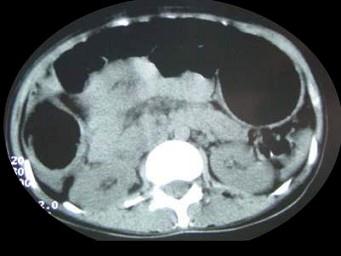

问题 女,30岁,便秘、腹痛腹胀多年,CT检查如图,最可能的诊断是 ( )

选项 A、结肠肠扭转 B、结肠肠栓塞 C、先天性巨结肠 D、结肠肠套叠 E、结肠肠梗阻

答案 C